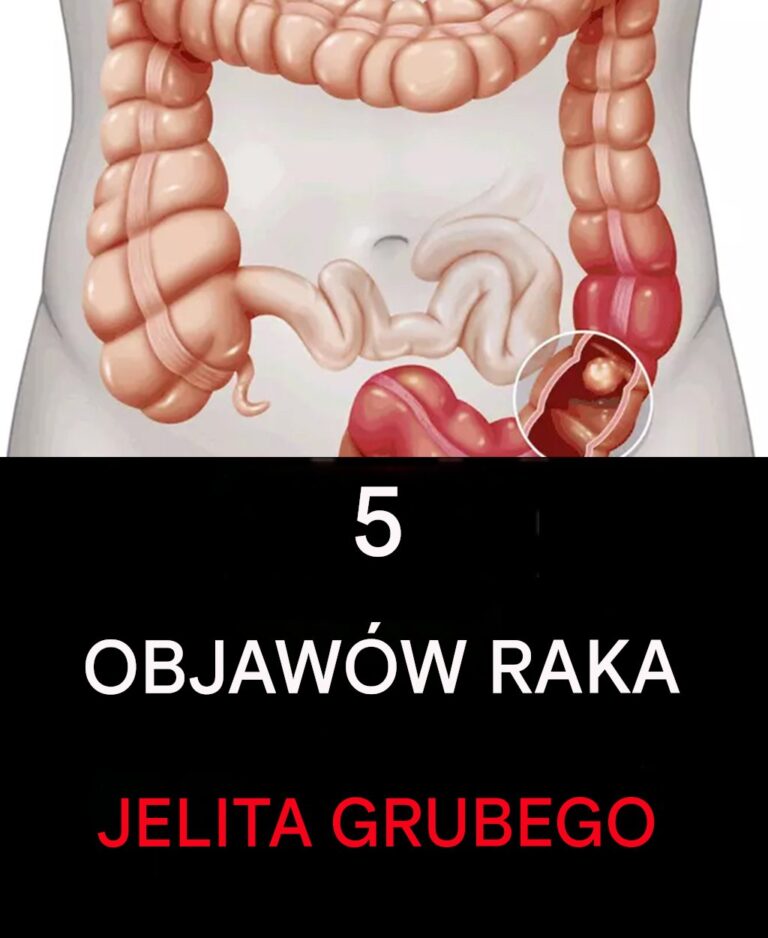

5 oznak raka jelita grubego

Choroby nowotworowe często atakują tam, gdzie najmniej się ich spodziewamy, a czasami nawet nie jesteśmy tego świadomi. Ponieważ objawy pojawiające się w miejscach, w…

Choroby nowotworowe często atakują tam, gdzie najmniej się ich spodziewamy, a czasami nawet nie jesteśmy tego świadomi. Ponieważ objawy pojawiające się w miejscach, w…